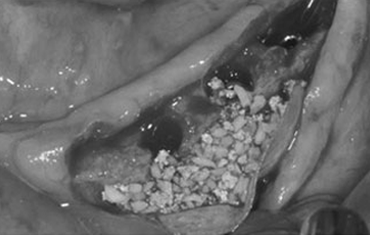

타 치과의 뼈 이식 후 골조직

램브란트치과 상인점 뼈이식 후 골조직

뼈의 소실량이 많은 경우

견고한 금속 차폐막 적용